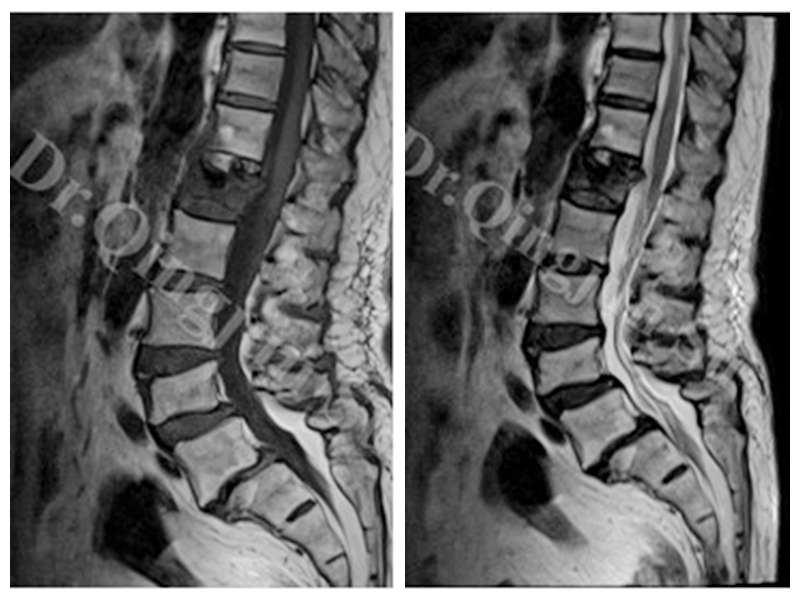

④在核磁上:诊断率最高,IVC主要有两种表现:当裂隙内主要是液体时,在T1上低信号,T2上高信号。(见上图)

当裂隙内是气体时,T1和T2相上均为低信号(见上图)。

•Yu等认为裂隙内液体征象和裂隙内气体征象是压缩骨折后椎体内骨坏死的两个阶段。早期出现液体征,随着塌陷的进展,裂隙周围的松质骨硬化、塌陷,阻止渗出液进入椎体,裂隙内出现气体。

•另一种观点认为,急性期患者伤椎周围水肿严重,患者仰卧位时液体快速积聚在裂隙内,此类患者核磁T2相上呈高信号;而骨折时间较长的患者仰卧位时,液体往往需要更长的时间才能慢慢聚集到裂隙内,核磁显示为T2相上的低信号。